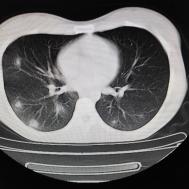

[影像描述]

两肺内及胸膜下多发斑片状高密度影,部分病灶密度较淡,部分实变,边缘可见渗出改变。